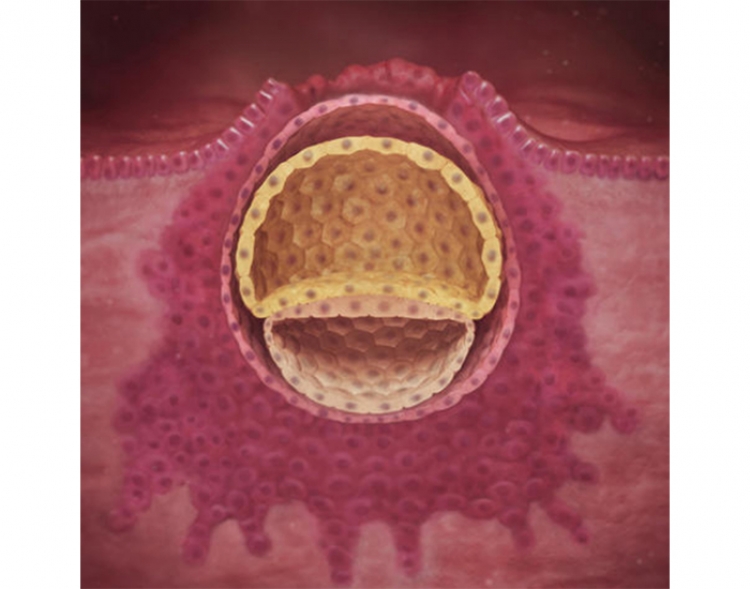

İçinde büyümekte olan embriyo henüz çok küçük. Hatta sadece bir grup hücreden oluşur, ancak bu hücreler çoğalmakta ve hızla büyümektedir. Gelişmekte olan hücre topuna zigot denir. Zigot, hücrelerin bölünmesi devam ederken rahim yolundan geçer ve rahme ulaşır.

Embriyo bir toplu iğne ucu büyüklüğündedir. Elbette hücre grubu henüz bir cenin ya da bebek görünümünde değildir. Bu ilk haftası boyunca embriyo yaklaşık 0.150 mm’dir.